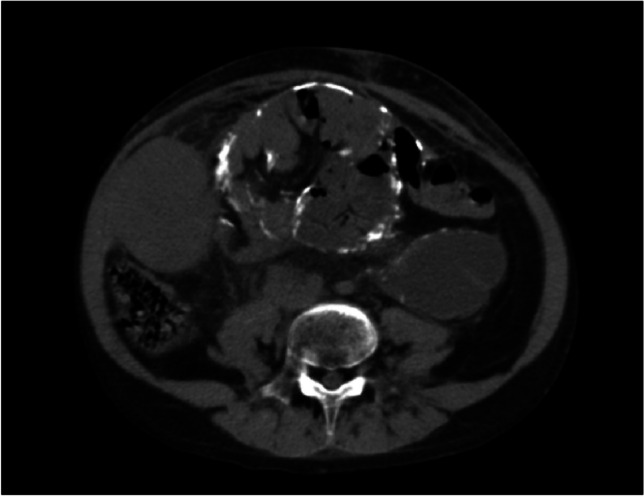

Abstract Image